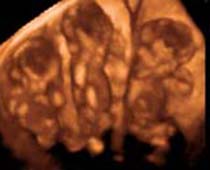

Clips vidéo 4D scan ultrason fœtal | Dr N Layyous

Clips vidéo 4D scan ultrason fœtal